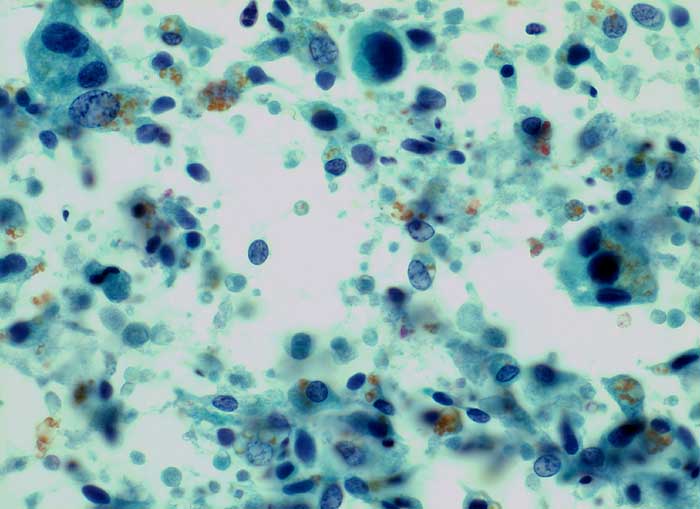

Adenokarzinom der Prostata / Samenblasenepithel

Die zytologische Diagnose des Prostatakarzinoms bereitet in der Regel keine grossen Schwierigkeiten. Die Karzinomzellen sind etwas grösser als normale Prostataepithelien. Die Kerne sind wenig grob strukturiert und ziemlich monomorph. Die Kern-Zytoplasma Relation ist erhöht. Nukleolen, die bereits bei 100 facher Vergrösserung gut sichtbar sind, stellen ein wichtiges Malignitätskriterium dar. Im Übrigen hängt das zytologische Bild von der Differenzierung des untersuchten Tumors ab.

Samenblasenepithelien können aufgrund ausgeprägter Atypien und manchmal erkennbaren Nukleolen mit Karzinomzellen verwechselt werden. Im Unterschied zu den Prostataepithelien enthält ihr Zytoplasma meist Lipofuszingranula.